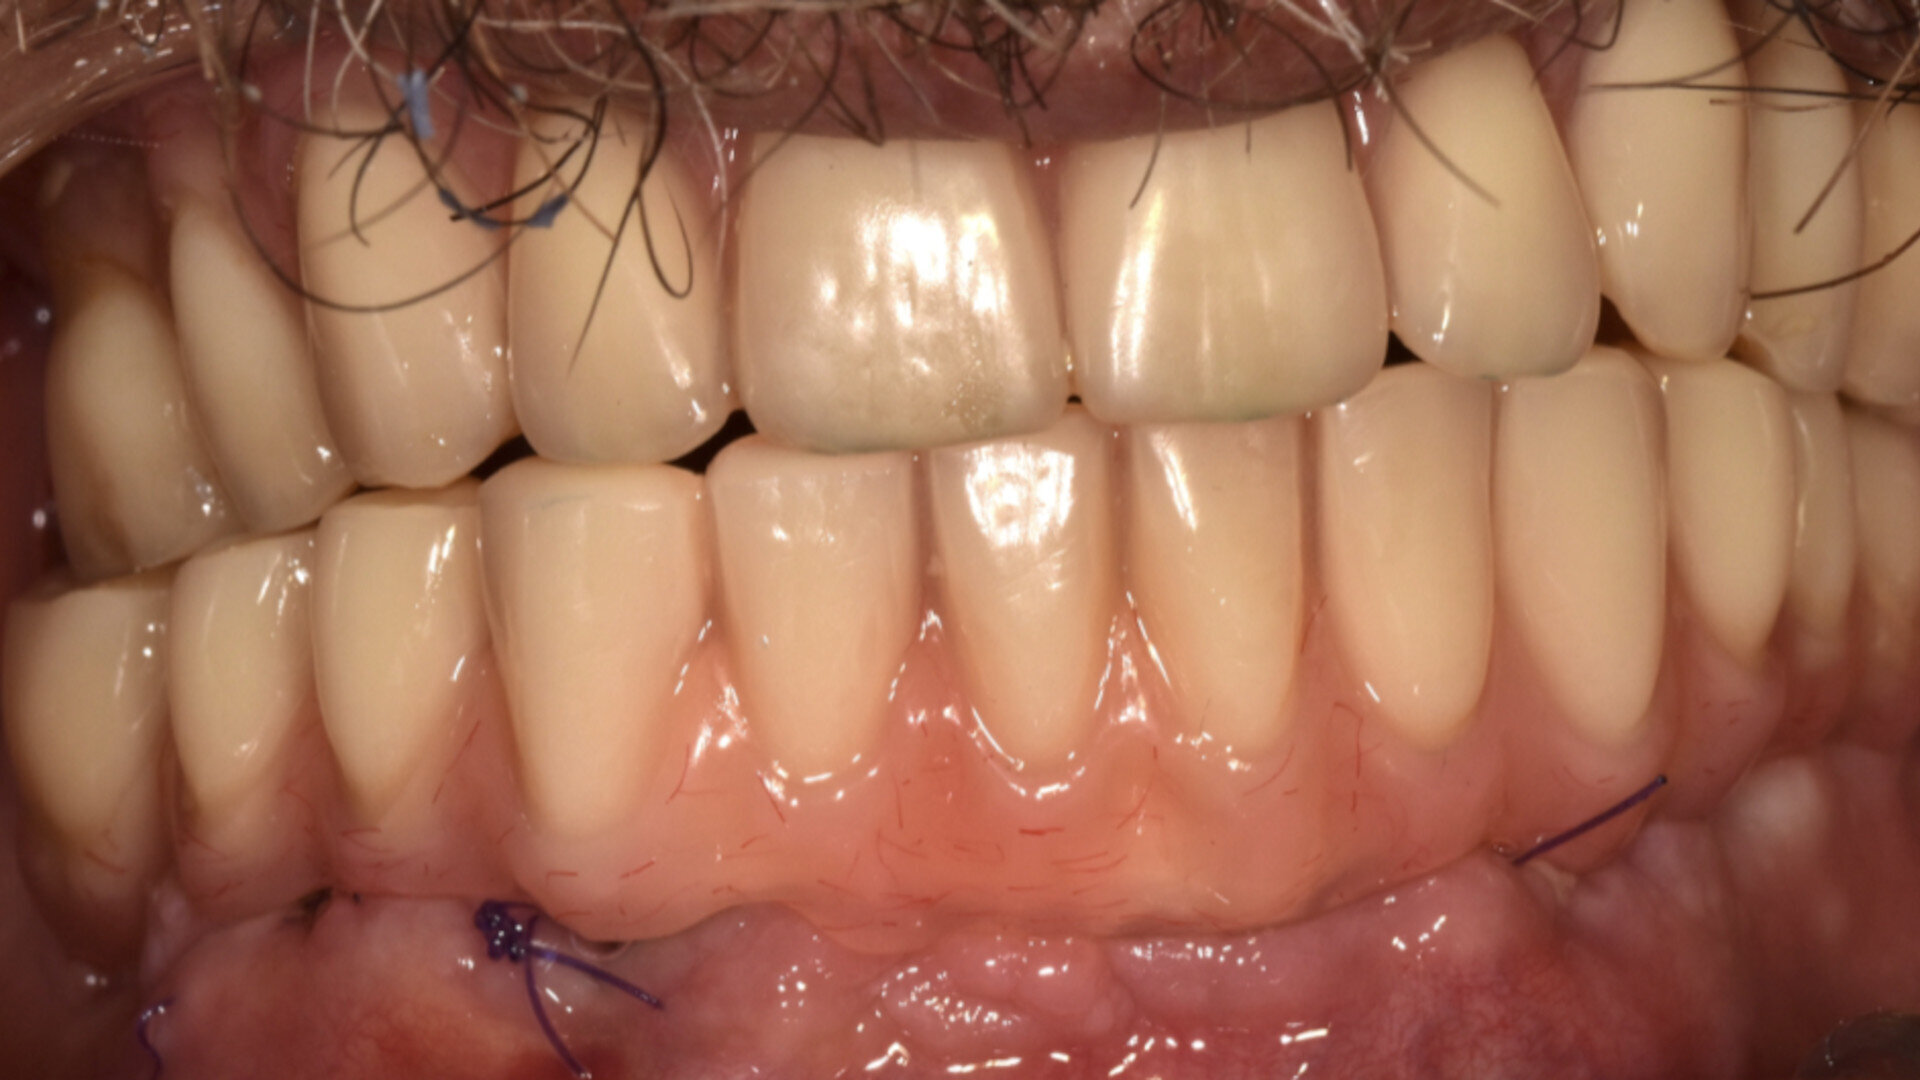

Fig. 1 : Bridges de transition CR/CO coulé/résine vissés en MCI.

Nous avons depuis la fin des années 1980 réalisé des prothèses avec succès en mise en fonction immediate après extractions et implantations. Celles-ci consistaient en une armature en CrCo coulée, sur laquelle étaient montées des dents du commerce, polymérisée en moufle de laboratoire. La rigidité de la contention était donc assurée, et la passivité de la structure obtenue par le collage de cylindres en titane dans l’armature, compensant ainsi les menues imperfections combines de l’empreinte, de la coulée du plâtre et de celle du métal (Fig. 1).

Le Zantex présente donc d’excellentes propriétés de résistance à la traction, de flexion et de compression, tout en ayant une faible densité, pour le confort du patient. Il est biocompatible, facilement réglable, et ne nécessite aucune cuisson, tout en fournissant un haut niveau de liberté de conception et de fabrication. Sa particularité est l’adhésion parfait et durable avec les matériaux utilisés en restauration dentaire. Pour la mise en oeuvre de nos MCI, le Zantex est usiné en armature sur laquelle sont monté des dents du commerce et acrylique, polymérisée en moufle de laboratoire. La rigidité de la contention est donc assurée, et la passivité de la structure obtenue par le collage de cylindres en titane à l’intrados de l’armature (Figs. 4–7).